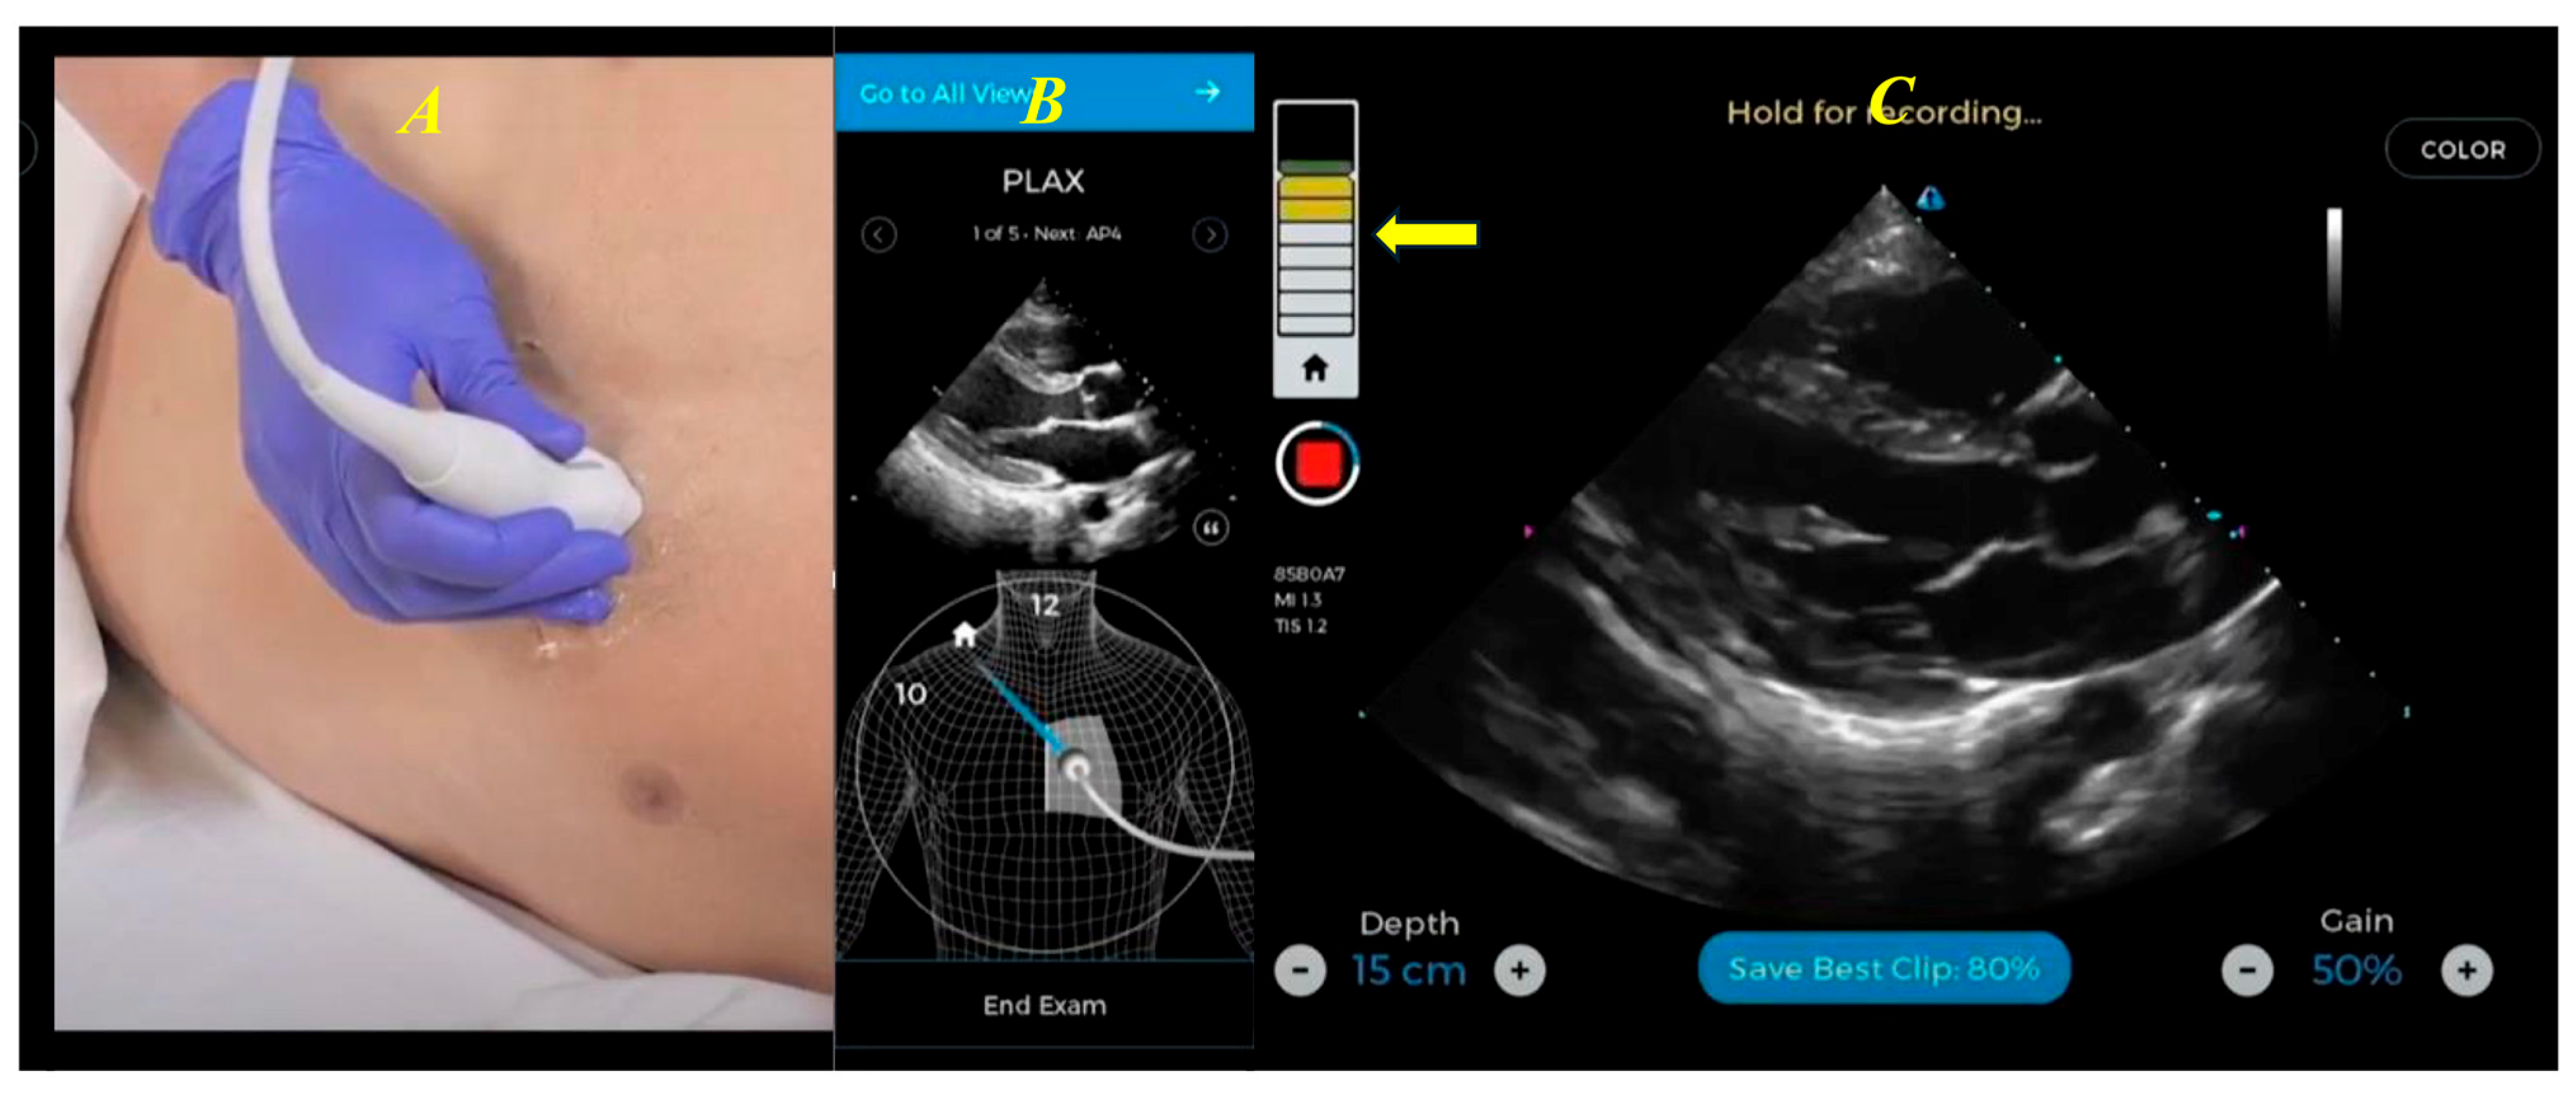

| Echocardiography (Figure 2, Figure 3, Figure 4 and Figure 5) |

- Narang, A.; Bae, R.; Hong, H.; Thomas, Y.; Surette, S.; Cadieu, C.; Chaudhry, A.; Martin, R.P.; McCarthy, P.M.; Rubenson, D.S.; et al. Utility of a Deep-Learning Algorithm to Guide Novices to Acquire Echocardiograms for Limited Diagnostic Use. JAMA Cardiol. 2021, 6, 624–632. [Google Scholar] [CrossRef]

- Mor-Avi, V.; Khandheria, B.; Klempfner, R.; Cotella, J.I.; Moreno, M.; Ignatowski, D.; Guile, B.; Hayes, H.J.; Hipke, K.; Kaminski, A.; et al. Real-Time Artificial Intelligence–Based Guidance of Echocardiographic Imaging by Novices: Image Quality and Suitability for Diagnostic Interpretation and Quantitative Analysis. Circ. Cardiovasc. Imaging 2023, 16, e015569. [Google Scholar] [CrossRef]

- Trost, B.; Rodrigues, L.; Ong, C.; Dezellus, A.; Goldberg, Y.H.; Bouchat, M.; Roger, E.; Moal, O.; Singh, V.; Moal, B.; et al. Artificial Intelligence Empowers Novice Users to Acquire Diagnostic-Quality Echocardiography. JACC Adv. 2025, 4, 102005. [Google Scholar] [CrossRef]